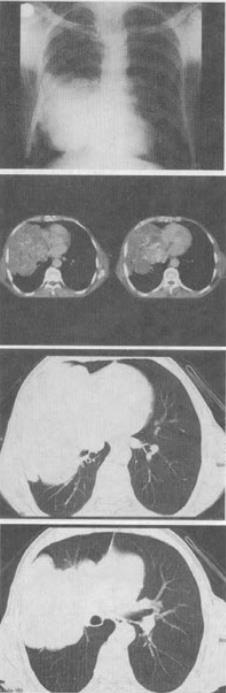

- 单项选择题 患者50岁,男,右侧胸痛、咳嗽、咯血3个月,结合胸片和CT检查,最可能的诊断是()。

- C